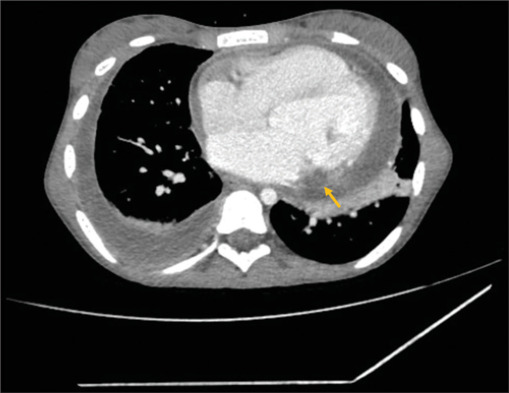

Figure 2.

Cardiac computerized tomography (axial section) showing a hypodense area with peripheral enhancement below the posterior mitral valve leaflet (arrow)

On examination, the patient was febrile, pulse rate was 134/min, respiratory rate was 33/min, oxygen saturation was 99% on room air, and blood pressure was 90/60 mm Hg. Her left knee had mild swelling. On auscultation, a holosystolic murmur of mitral regurgitation and bilateral basal crepitations over the lung fields were found. The chest X-ray showed cardiomegaly and mild pulmonary congestion. An electrocardiogram revealed sinus tachycardia with no chamber enlargements. The laboratory examination showed leukocytosis with a total leukocyte count of 18,260/mm3. Hemoglobin was 10.5 gm/dL. C-reactive protein was 228 mg/L. Two blood cultures grew S. maltophilia, a Gram-negative bacillus, sensitive to cotrimoxazole, levofloxacin, and minocycline but resistant to penicillin, cephalosporins, and vancomycin. The transthoracic echocardiogram demonstrated the presence of a large vegetation attached to the posterior mitral valve leaflet (PMVL), causing an eccentric jet of severe mitral regurgitation and moderate pericardial effusion. Adjacent to the PMVL, a hypoechoic shadow extending to the lateral left ventricular wall was noted, indicating a myocardial abscess [Figure 1 and Supplementary Video 1]. Cardiac computed tomography (CT) done subsequently also showed the evidence of an abscess as a hypodense area with peripheral enhancement below PMVL [Figure 2]. Additionally, a pseudoaneurysm arising superior to the mitral valve below the left atrial appendage was identified [Figure 3]. Evidence of septic pulmonary emboli was identified on the CT lung images.